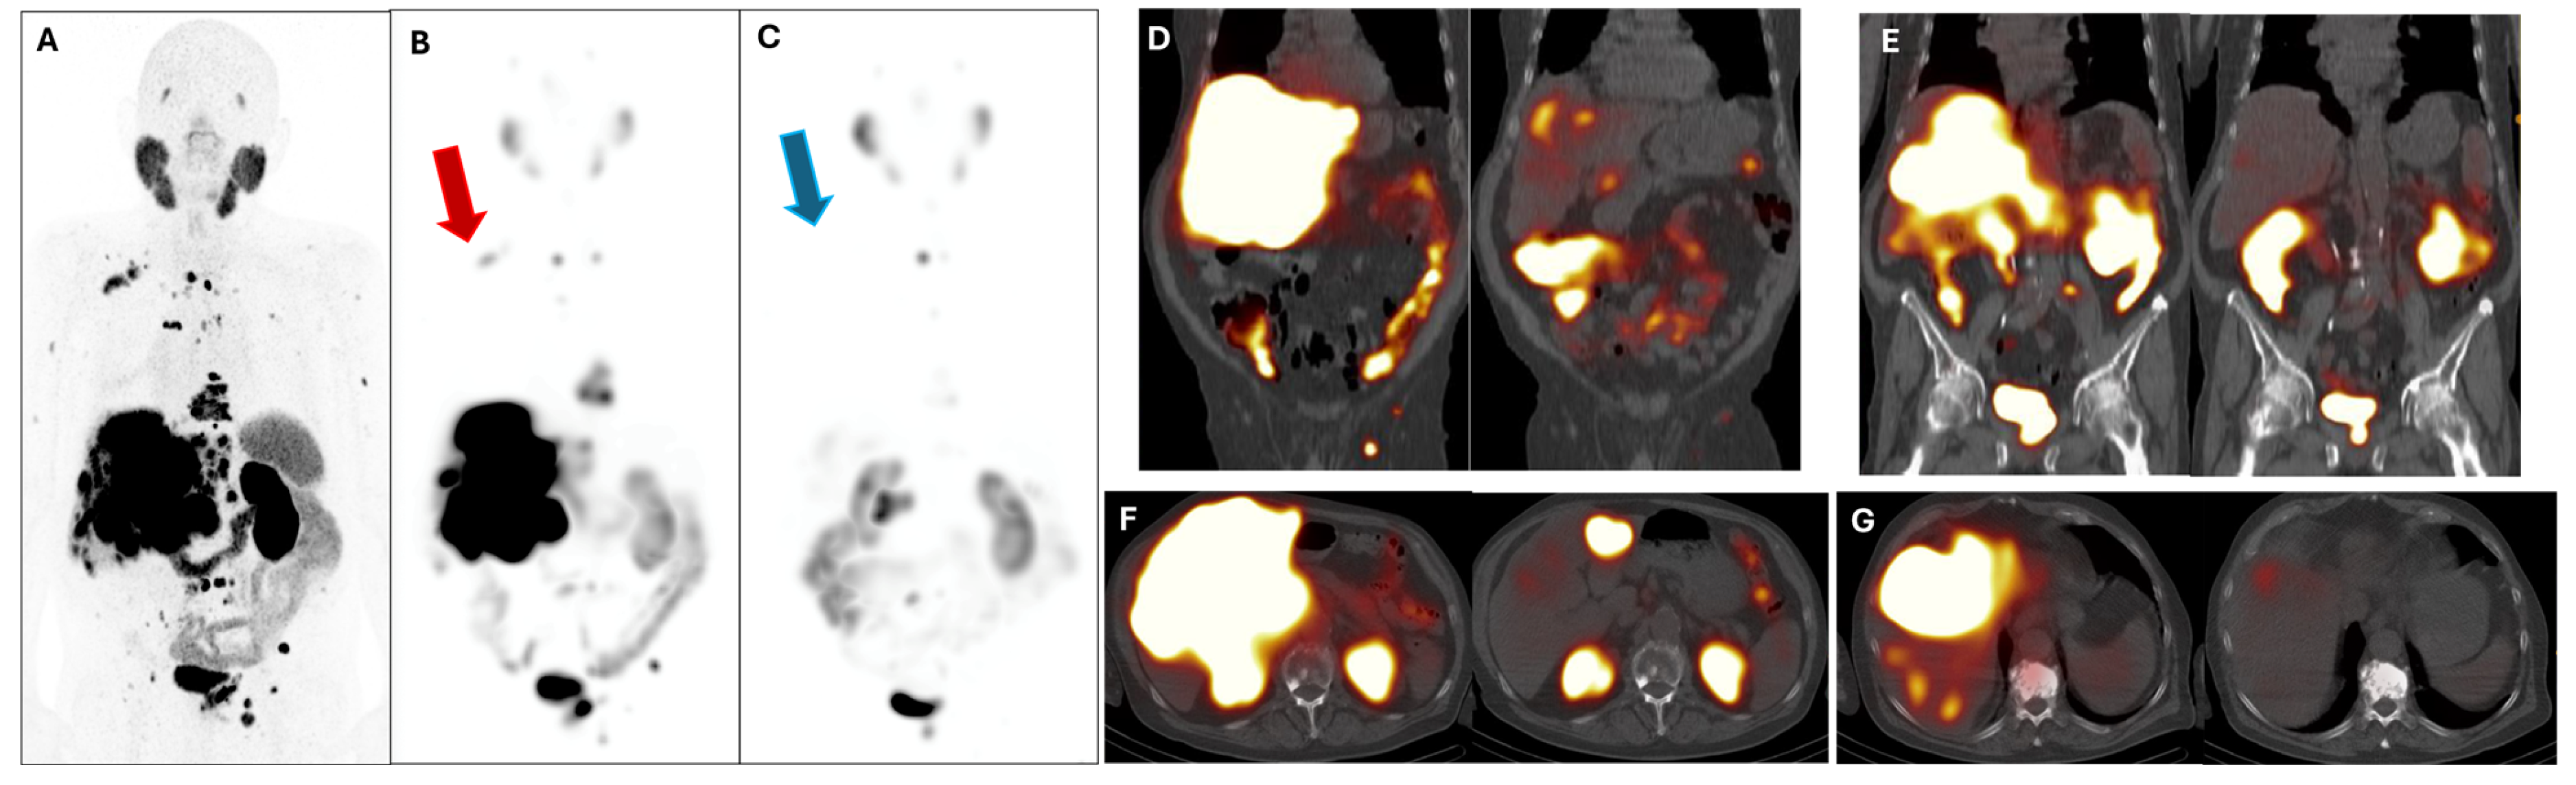

3. Results

| Degarelix, Denosumab, 6x Docetaxel, Leuprorelin, Abiraterone | 7BRCA 2, TMB 10.53 mut/Mb, VUS CHEK2, CDH1 | Bone and bone marrow | 4 | 83 | 96 |